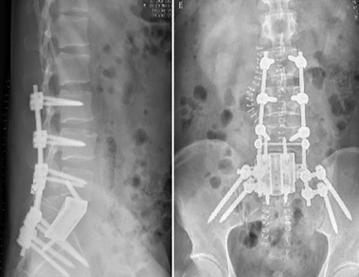

手術(shù)在新的一天的凌晨2點(diǎn)結(jié)束,術(shù)中跟臺(tái)護(hù)士更換了3批,患者翻身2次,歷時(shí)10余個(gè)小時(shí),生命體征未出現(xiàn)波動(dòng),患者在ICU病房幾小時(shí)后即拔管蘇醒。術(shù)后的患者如廁正常,并已下地活動(dòng),復(fù)查X光片,內(nèi)固定位置良好,假體完全貼合。